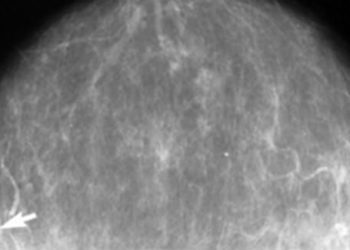

#VisualAbstract: Switch to fulvestrant and palbociclib may improve survival in patients with advanced breast cancer and ESR1 mutation